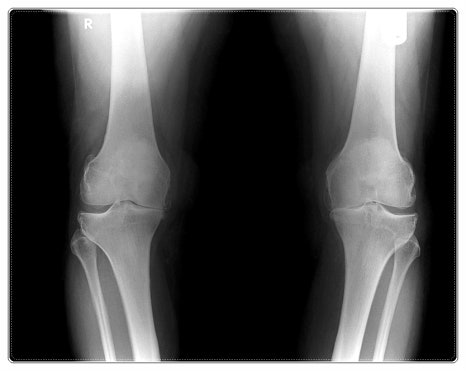

관절이 좀 아픈데… 그냥 참으면 괜찮아질까요?

관절은 자동차의 관절축과 비슷합니다.

평소에는 문제없어 보이다가도 사용이 몰리면 마모가 드러나듯,

몸도 회복할 틈 없이 쓰이면 통증으로 신호를 보냅니다.

주말에 통증이 더 심해지는 이유 역시 같습니다.

활동량은 늘어나는데, 회복할 시간은 줄어들기 때문입니다.

이런 통증을 그대로 두면 보통 다음과 같은 흐름을 겪게 됩니다.

✔ 1단계: 뻐근함과 뻣뻣함, 스트레칭으로 일시적 완화

✔ 2단계: 특정 동작에서 통증이 반복

✔ 3단계: 일상에 통증이 개입되고 움직임 감소, 수면 방해

많은 분들이 2단계에서

“조금만 더 참아보자”라는 선택을 하곤 합니다.

그리고 나중에 상태를 설명 들었을 때,

생각보다 더 진행되어 있었다는 사실에 놀라시는 경우도 적지 않습니다.

무릎이 아프다고 해서 무릎만, 어깨가 불편하다고 해서 어깨만 보지는 않습니다.

예를 들어 무릎 통증이 발 사용 습관이나

골반의 불균형과 연결되어 있는 경우도 적지 않습니다.